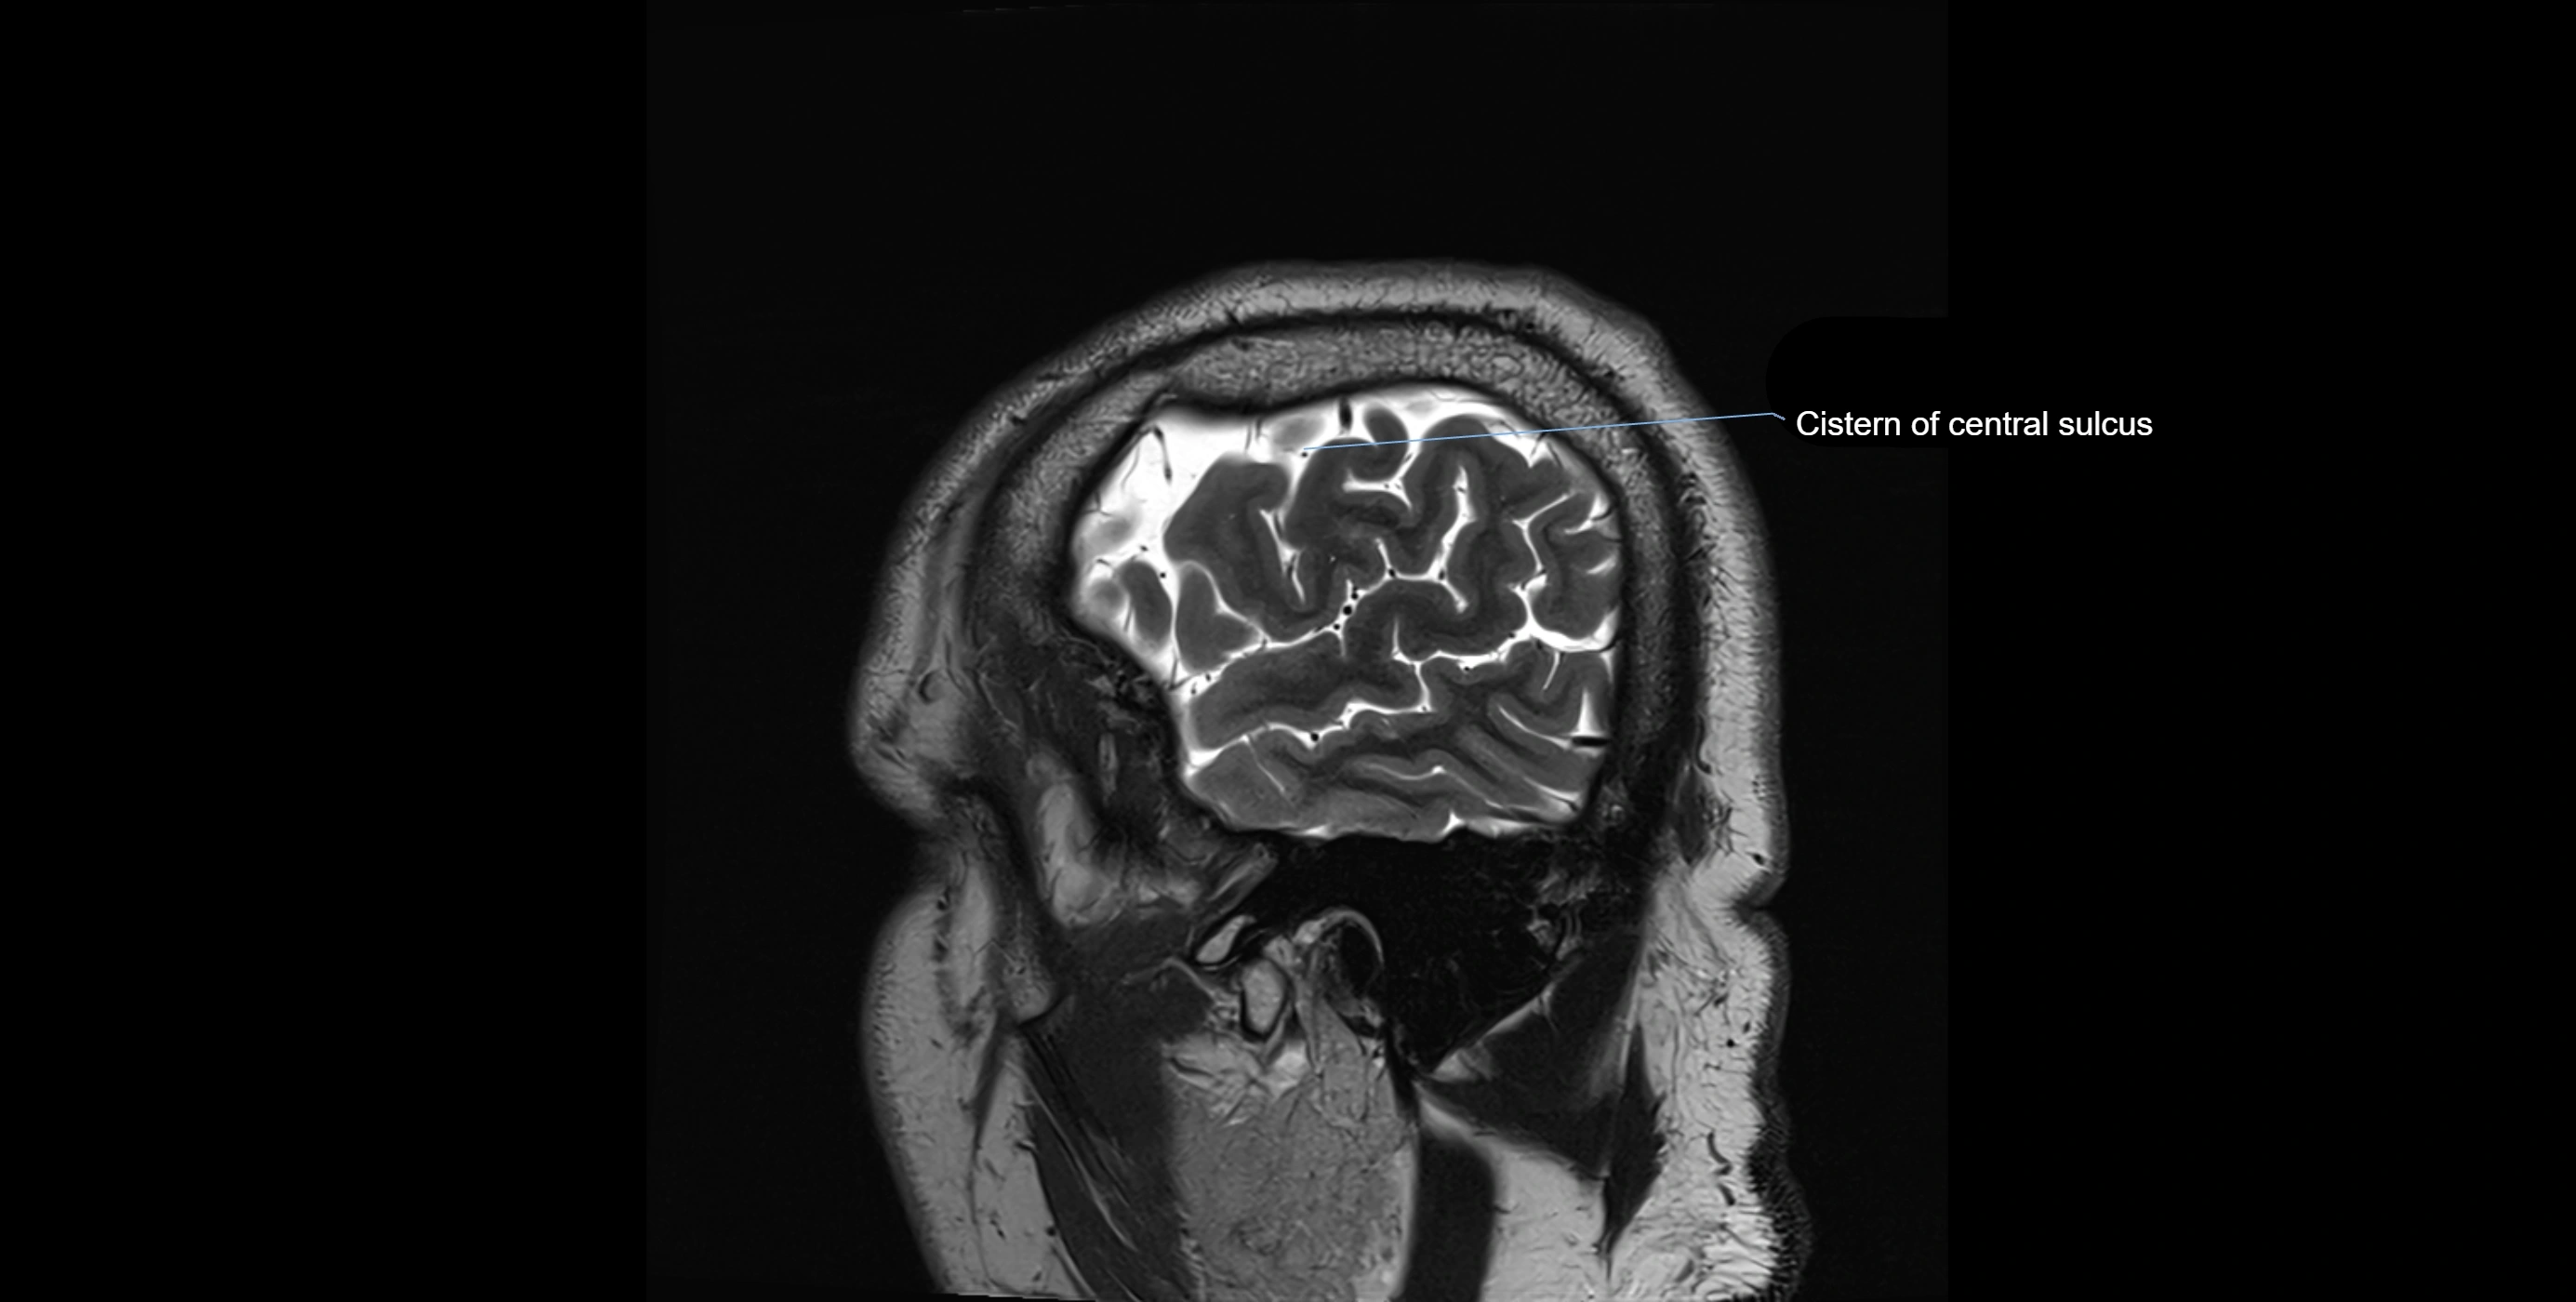

MRI images

image